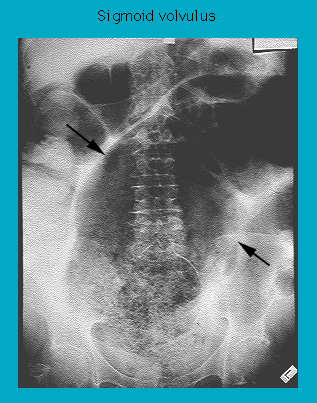

Abdominal radiograph in sigmoid volvulus